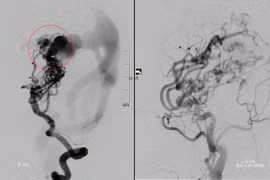

Bệnh nhi bị xuất huyết não nguy kịch do vỡ khối dị dạng thông động tĩnh mạch não.

(VietnamDaily) - Ra sân đá bóng nhưng chưa kịp đá, cậu bé 15 tuổi phải trở về nhà vì lên cơn đau đầu đột ngột, nôn, cạo gió không đỡ, gia đình đưa lên viện thì biết con bị đột quỵ.

Ra sân đá bóng nhưng chưa kịp đá, cậu bé 15 tuổi phải trở về nhà vì lên cơn đau đầu đột ngột, nôn, cạo gió không đỡ, gia đình đưa lên viện thì biết con bị đột quỵ.